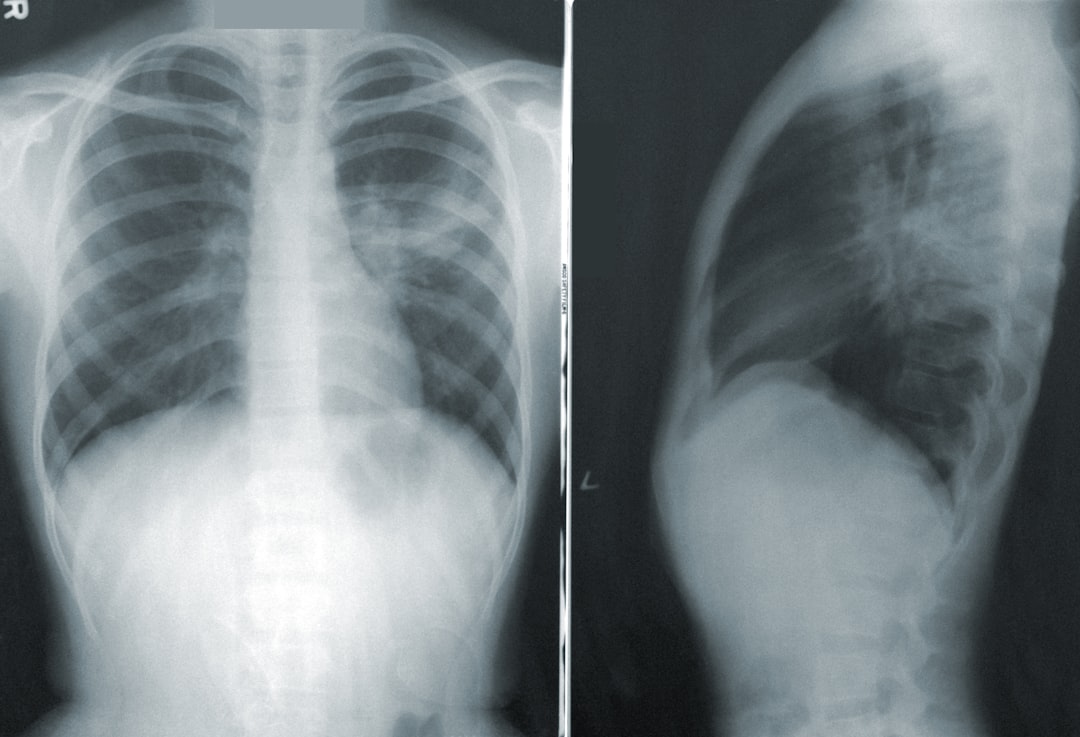

폐렴은 우리의 호흡기에 영향을 미치는 질병으로, 다양한 증상이 나타날 수 있습니다. 초기 신호와 대처법을 알아보아, 건강을 지키는 데 도움이 되길 바랍니다.

폐렴 증상 이해하기

폐렴증상은 초기에는 가벼운 기침이나 기침에서 시작될 수 있습니다. 그러나 이 기침이 계속되거나 심해지면, 곧 다른 증상들이 이어질 수 있습니다. 폐렴 증상 중에는 고열, 몸살, 그리고 숨가쁨이 포함되어 있습니다. 또한, 이 질병은 노인들에게는 특히 위험한데, 그 이유는 면역력이 약해 손쉽게 감염될 수 있기 때문입니다. 따라서 가족이나 친구의 상태를 잘 관찰해야 합니다. 이러한 폐렴증상들은 단순한 감기랑 비슷하게 시작되기 때문에 주의 깊은 관리가 필요합니다.